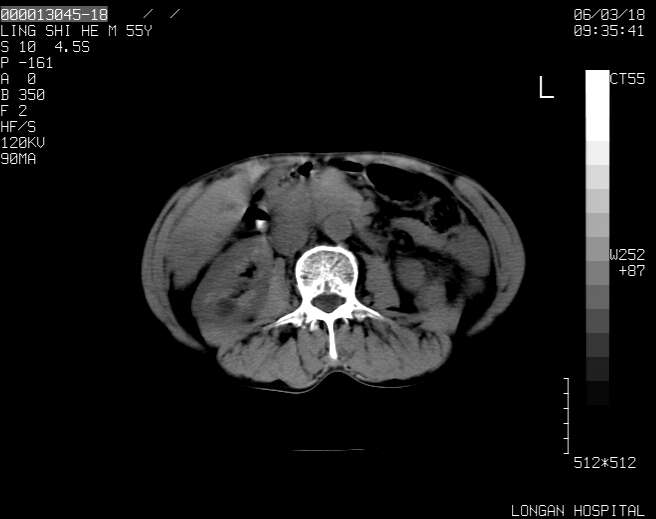

以下是引用guzhongliangddd在2006-3-21 22:13:00的发言:[br]病灶主要位于肝右叶的后份,内见异常血管,门脉主干及右支受侵{提示有癌栓形成},门腔间隙内见增大淋巴结。肝左叶内未见异常。

以下是引用zhuxinli在2006-3-22 1:23:00的发言:[br][br] 病灶主要位于肝右叶的后份,内见异常血管 .门脉右支截断,右叶前段早期强化(考虑动静脉漏),腹膜后肿大淋巴结,病灶逐渐强化,考虑为胆管细胞癌[br]